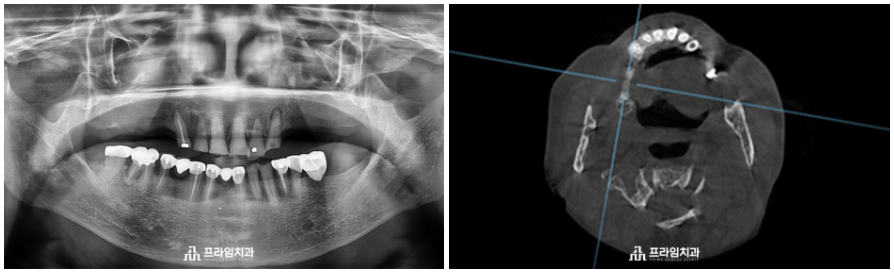

위 환자분은 88세 여성분으로

전주에 혼자 거주하고 계시는 분이신데요.

치과 공포증으로 인해 여태까지

치료를 미루고 계셨다고 하셨습니다.

.

윗니가 앞니 6개만 남아 있는 채로

10년 넘게 앞니로만 식사를 하고 계신 상태로

경제적인 여유가 충분하나 임플란트 수술이 무서워

치료를 포기하고 계시다가 큰마음 먹고

임플란트를 하기로 결정하고 난 후

자제분이 계신 서울의 치과 몇 군데에서

상담을 받으시고 오셨다고 하셨습니다.

그러던 중 저희 치과에 내원해 주셨고

무절개임플란트에 관한 설명을 들으시고

타치과에서는 잇몸뼈 이식을 해야 한다고

설명 들으셨지만

잇몸뼈 이식 없는

매직 코어를 이용한 본원의 편안한 임플란트

설명을 들으시고 진행하기로 하였습니다.

환자분의 잇몸 상태를 충분히

고려하여 전주임플란트치과에서는

매직 코어 최소침습 임플란트

수술의 장점을 설명드린 후

진행하였습니다.